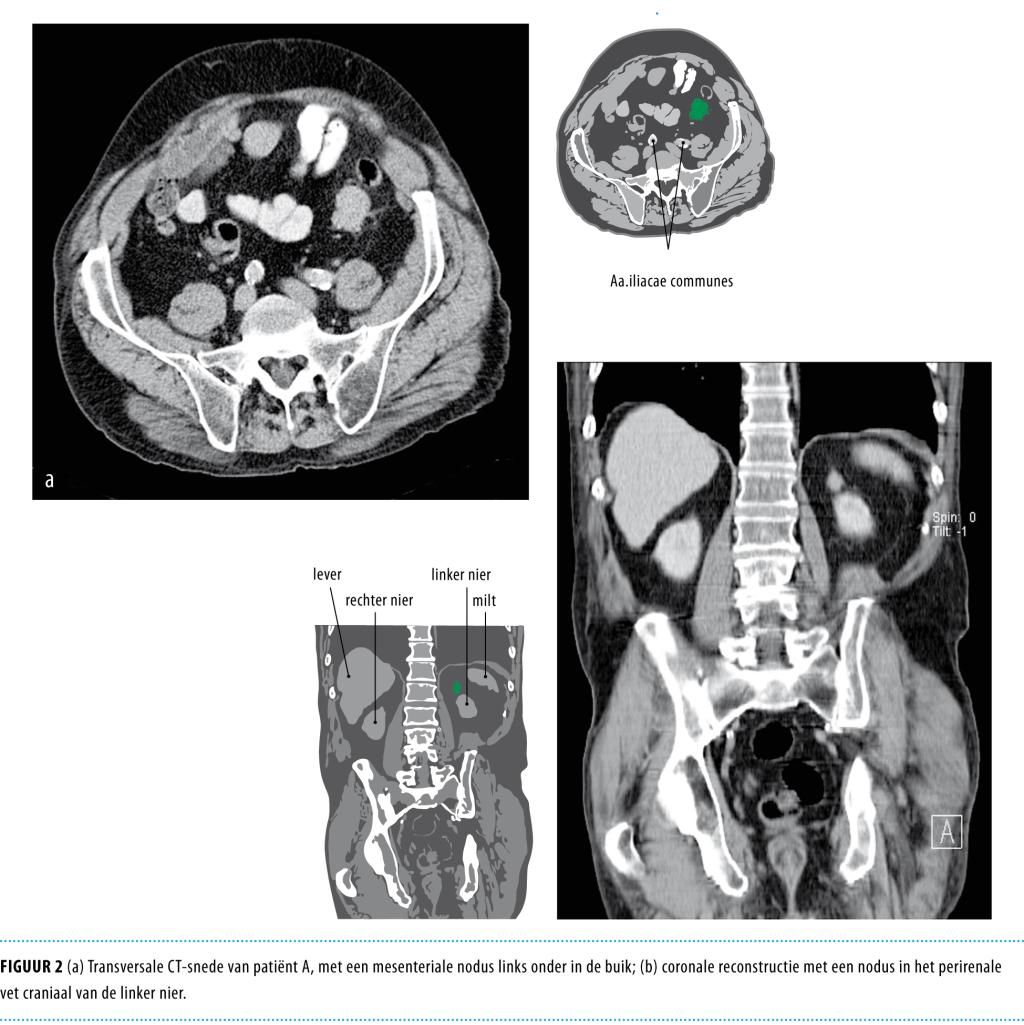

Een 73-jarige man had een solide nodus op de rechter bovenarm, die bleek te berusten op een merkelcel-carcinoom (MCC). De diagnose werd gesteld op grond van kenmerkende histopathologische bevindingen en een ruime chirurgische excisie volgde. Na 20 maanden manifesteerde zich een forse zwelling in de rechter oksel door een metastase. Bij CT van de thorax en het abdomen werden 2 verdachte afwijkingen gezien in respectievelijk het mesenteriale vet in de linker onderbuik en in het perirenale vet links. Een onder CT-geleide genomen biopt van de laatste afwijking bevestigde dat het ging om een metastase van het MCC. Patiënt werd bestraald, maar zag af van chemotherapie. Hij overleed 2 jaar na de diagnose. MCC is een zeldzame agressieve vorm van maligne ontaarding van de huid. Vroege herkenning maakt curatie mogelijk. De behandeling is multidisciplinair, maar chirurgie, al of niet in combinatie met radiotherapie, vormt de basis van behandeling voor zowel lokale als regionale ziekte. Gedissemineerde ziekte kan met succes worden bestreden met chemotherapie, maar het effect is tijdelijk. De 10-jaaroverleving varieert van 20-70%, afhankelijk van het ziektestadium.